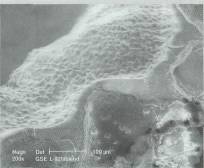

Bu projede, biyobozunur biyopolimerler üzerine yerleştirilen karaciğer hücrelerinin çoğalmaları, dokusal organizasyonu tamamlayarak işlevsel bir yapay karaciğer oluşturmaları amacıyla, hücre kültürü (in vitro) ve canlı hayvan deneylerinin (in vivo) gerçekleştirilmesi hedeflenmekte. Hücrelerin elde edilmesi ve hayvan deneyleri için, bir laboratuvar deney hayvanı olan Sprague-Daw-ley sıçanları kullanılıyor.

Hedefe varmak için birbirinden farklı üç alanda deneyler yapılıyor. Bunlardan biri, biyobozunur biyopolimerlerin oluşturulması. Bunlar, üzerine eklenen sağlıklı hücrelerin tutunup çoğalması için bir destek, iskelet işlevi üstleniyor ve hücrelerin çoğalıp istenen organın hacmi ve işlevine erişme sürecine paralel olarak, vücutta reaksiyon yaratmayan küçük moleküllere ayrışarak ortadan kalkıyorlar. Projede bu biyopolimerler, dünyada da bu amaçla çok kullanılan laktik ve glikolik asit monomerleriyle oluşturuluyorlar; ancak, hücrelerin özgün olarak bu yapıya tutunmalarını sağlayacak molekülleri de bu polimerle-re katmak yoluyla, bu çalışmalar bir ileri aşamaya taşınmış durumda.

Vücudumuzdaki dokularda hücrelerin tutunmaları, çeşitli proteinlerden oluşan ve hücre-dışı matriks (extra-cellular matrix/ESM) olarak adlandırılan bir organize protein tabakasıyla etkileşim yoluyla gerçekleşiyor. Bu, hücre yüzeyindeki proteinlerin ESM proteinleriyle etkileşimlerine dayanıyor ve hücrenin bulunduğu dokunun içindeki yerini belirlemesini, bir anlamda "hissetmesini" sağlıyor. Doku mühendisliğinde çözümlenmesi gereken temel sorun, hücrelerin bulundukları yeri doğru algılayarak hem özgün olarak tutun-

malarını sağlayan, hem de fenotiplerinin; yani belirli bir hücreyi o hücre yapan özelliklerin kaybolmasını önleyen bir biyomateryali oluşturabilmek ve kullanmak. Bu amaçla, ESM proteinlerine ait peptit dizileri, grubumuzda oluşturulan bi-yopolimerlere ekleniyor.

Bir diğer çalışma konusu, karaciğer hücreleri (hepatositler)'dir. Projede kullanılan karaciğer hücreleri, sağlıklı hayvanlardan enzim perfüzyo-nuyla izole edilerek kültür ortamında inceleniyorlar. Bu hücreler, bulundukları dokudan çıkarılarak yerleştirildikleri kültür ortamında, fenotiple-rini yani karaciğer hücresi olma özelliklerini hızla kaybederler. Bunu önlemek amacıyla çeşitli yaklaşımlar denenmekte. Bu da dünyada üzerinde çok çalışılan bir sorun. Bu değişimleri hücrelerde gen ve protein ifadeleri ölçülerek izleniyor. Bu amaçla, modern moleküler biyoloji yöntemleri olan kantitatif revers transkriptaz-polimeraz zincir reaksiyonu (hücrelerdeki mRNA'ların izolasyonu, bunlardan cDNA oluşturulması ve sonrasında ilgilenilen genin polimeraz zincir reaksiyonuyla çoğaltılarak ölçülebilir hale getirilmesi yöntemi, Q RT-PZR) ve Western blotlama (hücrelerdeki tüm proteinlerin izolasyonu, jel elektrofore-zi ile ayrılmaları, bir zara transfer edildikten sonra ilgilenilen proteinin peroksidaz ya da kemilü-